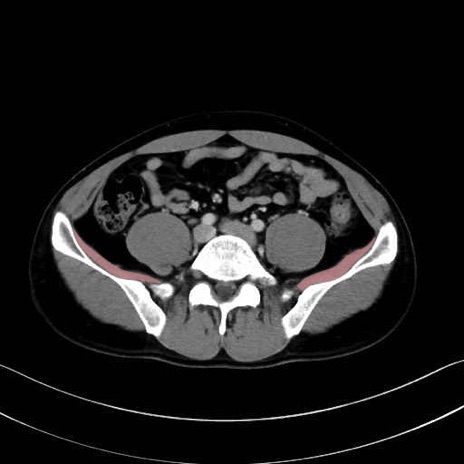

大腰筋 (Psoas major)

腸骨筋 (Iliacus)